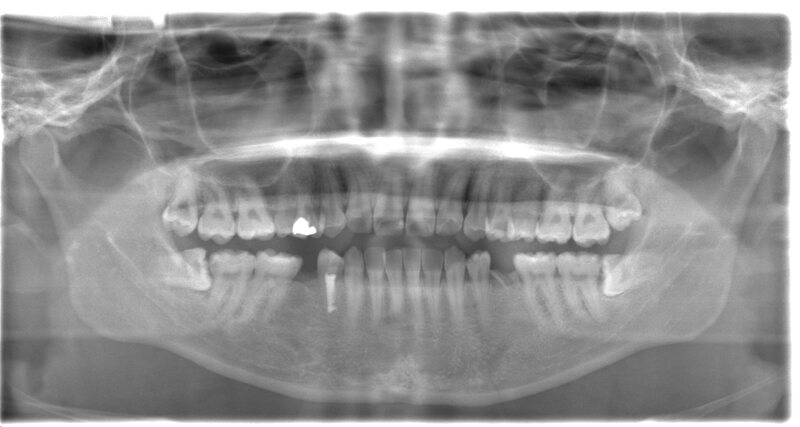

親知らずの根が太く曲がっていたため歯ぐきを切開し歯を分割して抜歯、2針縫合。痛みも出血もほとんどありませんでした。

治療前パノラマ

治療後CT

| 年齢・性別 | 50代・女性 |

|---|---|

| 主訴 | 左下親知らず欠けた・左下8 |

| 治療内容 | 左下親知らず抜歯 |

| 治療期間 | 1回約30分 |

| 治療費 | 8,000円(2022年5月現在) |

| リスク・副作用 | 2〜3日は腫れと痛みがある。 |

| 治療方針 | 事前にCT撮影を行い歯の状態・神経との位置関係を確認して抜歯をした。 |